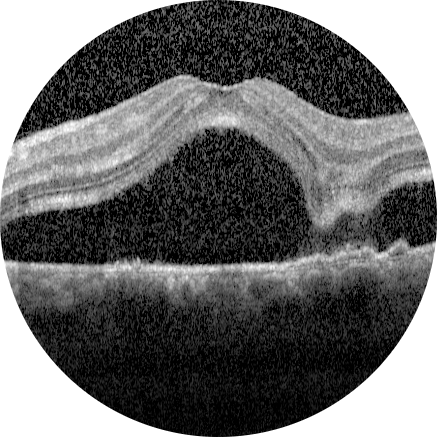

2026 Nisan Ayın Sorusu

Her iki gözde doğuştan bu yana görme problemleri olan 11 yaşındaki erkek hastanı ...